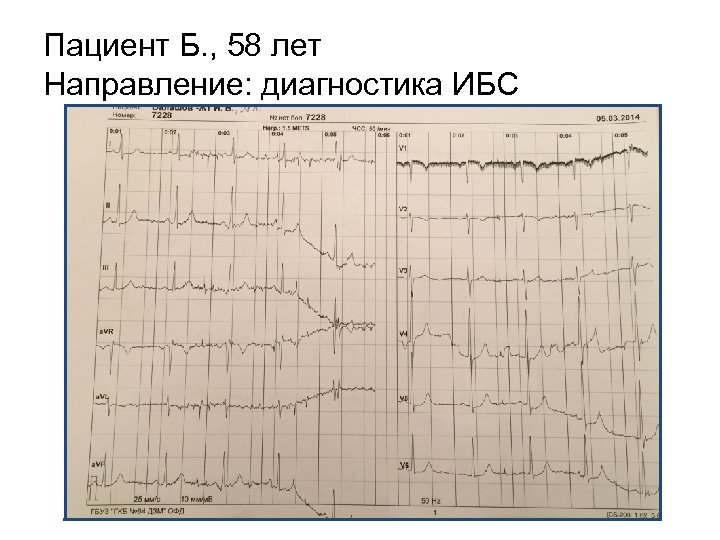

Пациент Б. , 58 лет Направление: диагностика ИБС

Пациент Б. , 58 лет Направление: диагностика ИБС